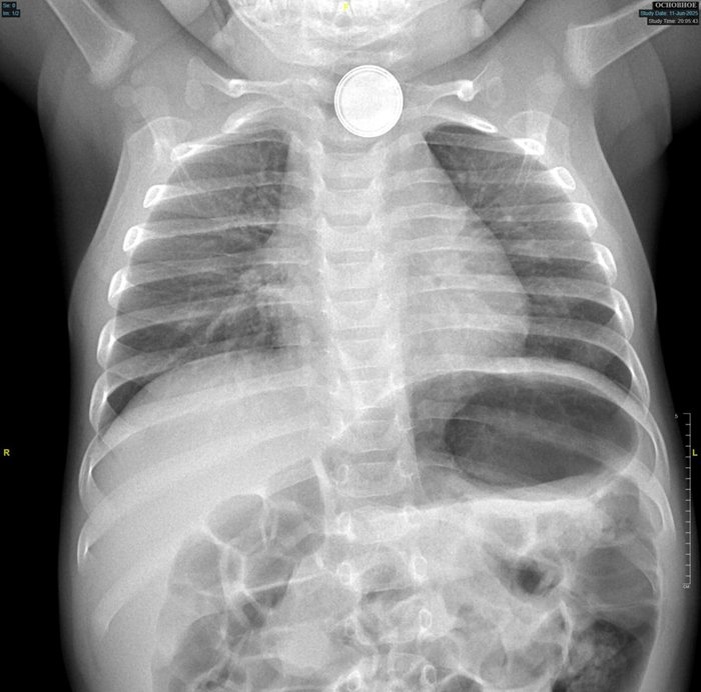

Сургутские врачи спасли 11-месячного малыша, проглотившего батарейку

После того, как родители обнаружили, что кроха проглотил круглую батарейку, пострадавшего доставили в Нефтеюганскую районную больницу. Рентген подтвердил наличие металлического инородного тела в верхней части пищевода. Попытки извлечь батарейку эндоскопическим путем в Нефтеюганске не увенчались успехом, и врачи приняли решение о срочной транспортировке ребенка в Сургут.

В Центре охраны материнства и детства малыша уже ждали. Экстренное эндоскопическое исследование показало, что инородное тело – аккумулятор диаметром 1,5 см – окружено налетом. Ситуация осложнялась электрохимическим ожогом пищевода 3 степени.

Врачи приняли решение срочно удалять батарейку хирургическим путем. Хирург Эльнур Джафаров выполнил лапаротомию и гастротомию и удалил опасный инородный предмет.

Послеоперационный период прошел успешно. Контрольное обследование спустя месяц показало отличные результаты: рубцовых сужений пищевода не выявлено, что свидетельствует о полном восстановлении его проходимости. Сейчас малыш дома и находится под амбулаторным наблюдением по месту жительства.